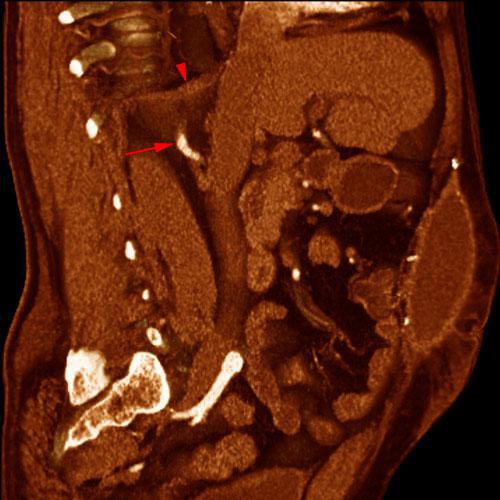

Arteria renal torácica

VR seccional. Visión sagital derecha. AngioTC renal mostrando el paso de la arteria renal derecha (flecha) a través del pilar diafragmático derecho (punta de flecha). Absceso de pared abdominal anterior